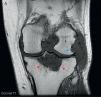

Given the radiological lesions of the left knee, we completed the study with a left knee MRI (Fig. 3) which showed synovial proliferation which revealed diffuse, hypointense lesions on T1, with bone erosions in the posterolateral margin of the femoral condyle. A large Baker's cyst with areas of high and low signal on T2 were seen, as well as lytic, hypointense lesion on T1, T2 with a heterogeneous signal level on the proximal tibial epiphysis and a maximum diameter of 5cm that after administration of gadolinium showed enhancement, something characteristic of tophaceous deposits.

(A) Left knee coronal T1MRI. It shows a diffuse hypointense synovial proliferation with bone erosion of the posterolateral margin of the femoral condyle (blue arrow) and intercondylar notch. A hypointense lytic lesion is seen in the proximal tibial epiphysis with a maximum diameter of 5cm (red arrows). (B) Sagittal T2. There is an increased signal heterogeneity at the level of the tibial epiphyseal lytic lesion (red arrows), along with a large Baker's cyst located behind the medial gastrocnemius muscle (green arrows), with areas of high and low signal for synovial hypertrophy. (C) Sagittal T1-Gd. After administration of gadolinium, enhancement shows the level of peripheral tibial lytic lesion (red arrows) and Baker's cyst (green arrows). (For interpretation of the references to color in this figure legend, the reader is referred to the web version of the article.)